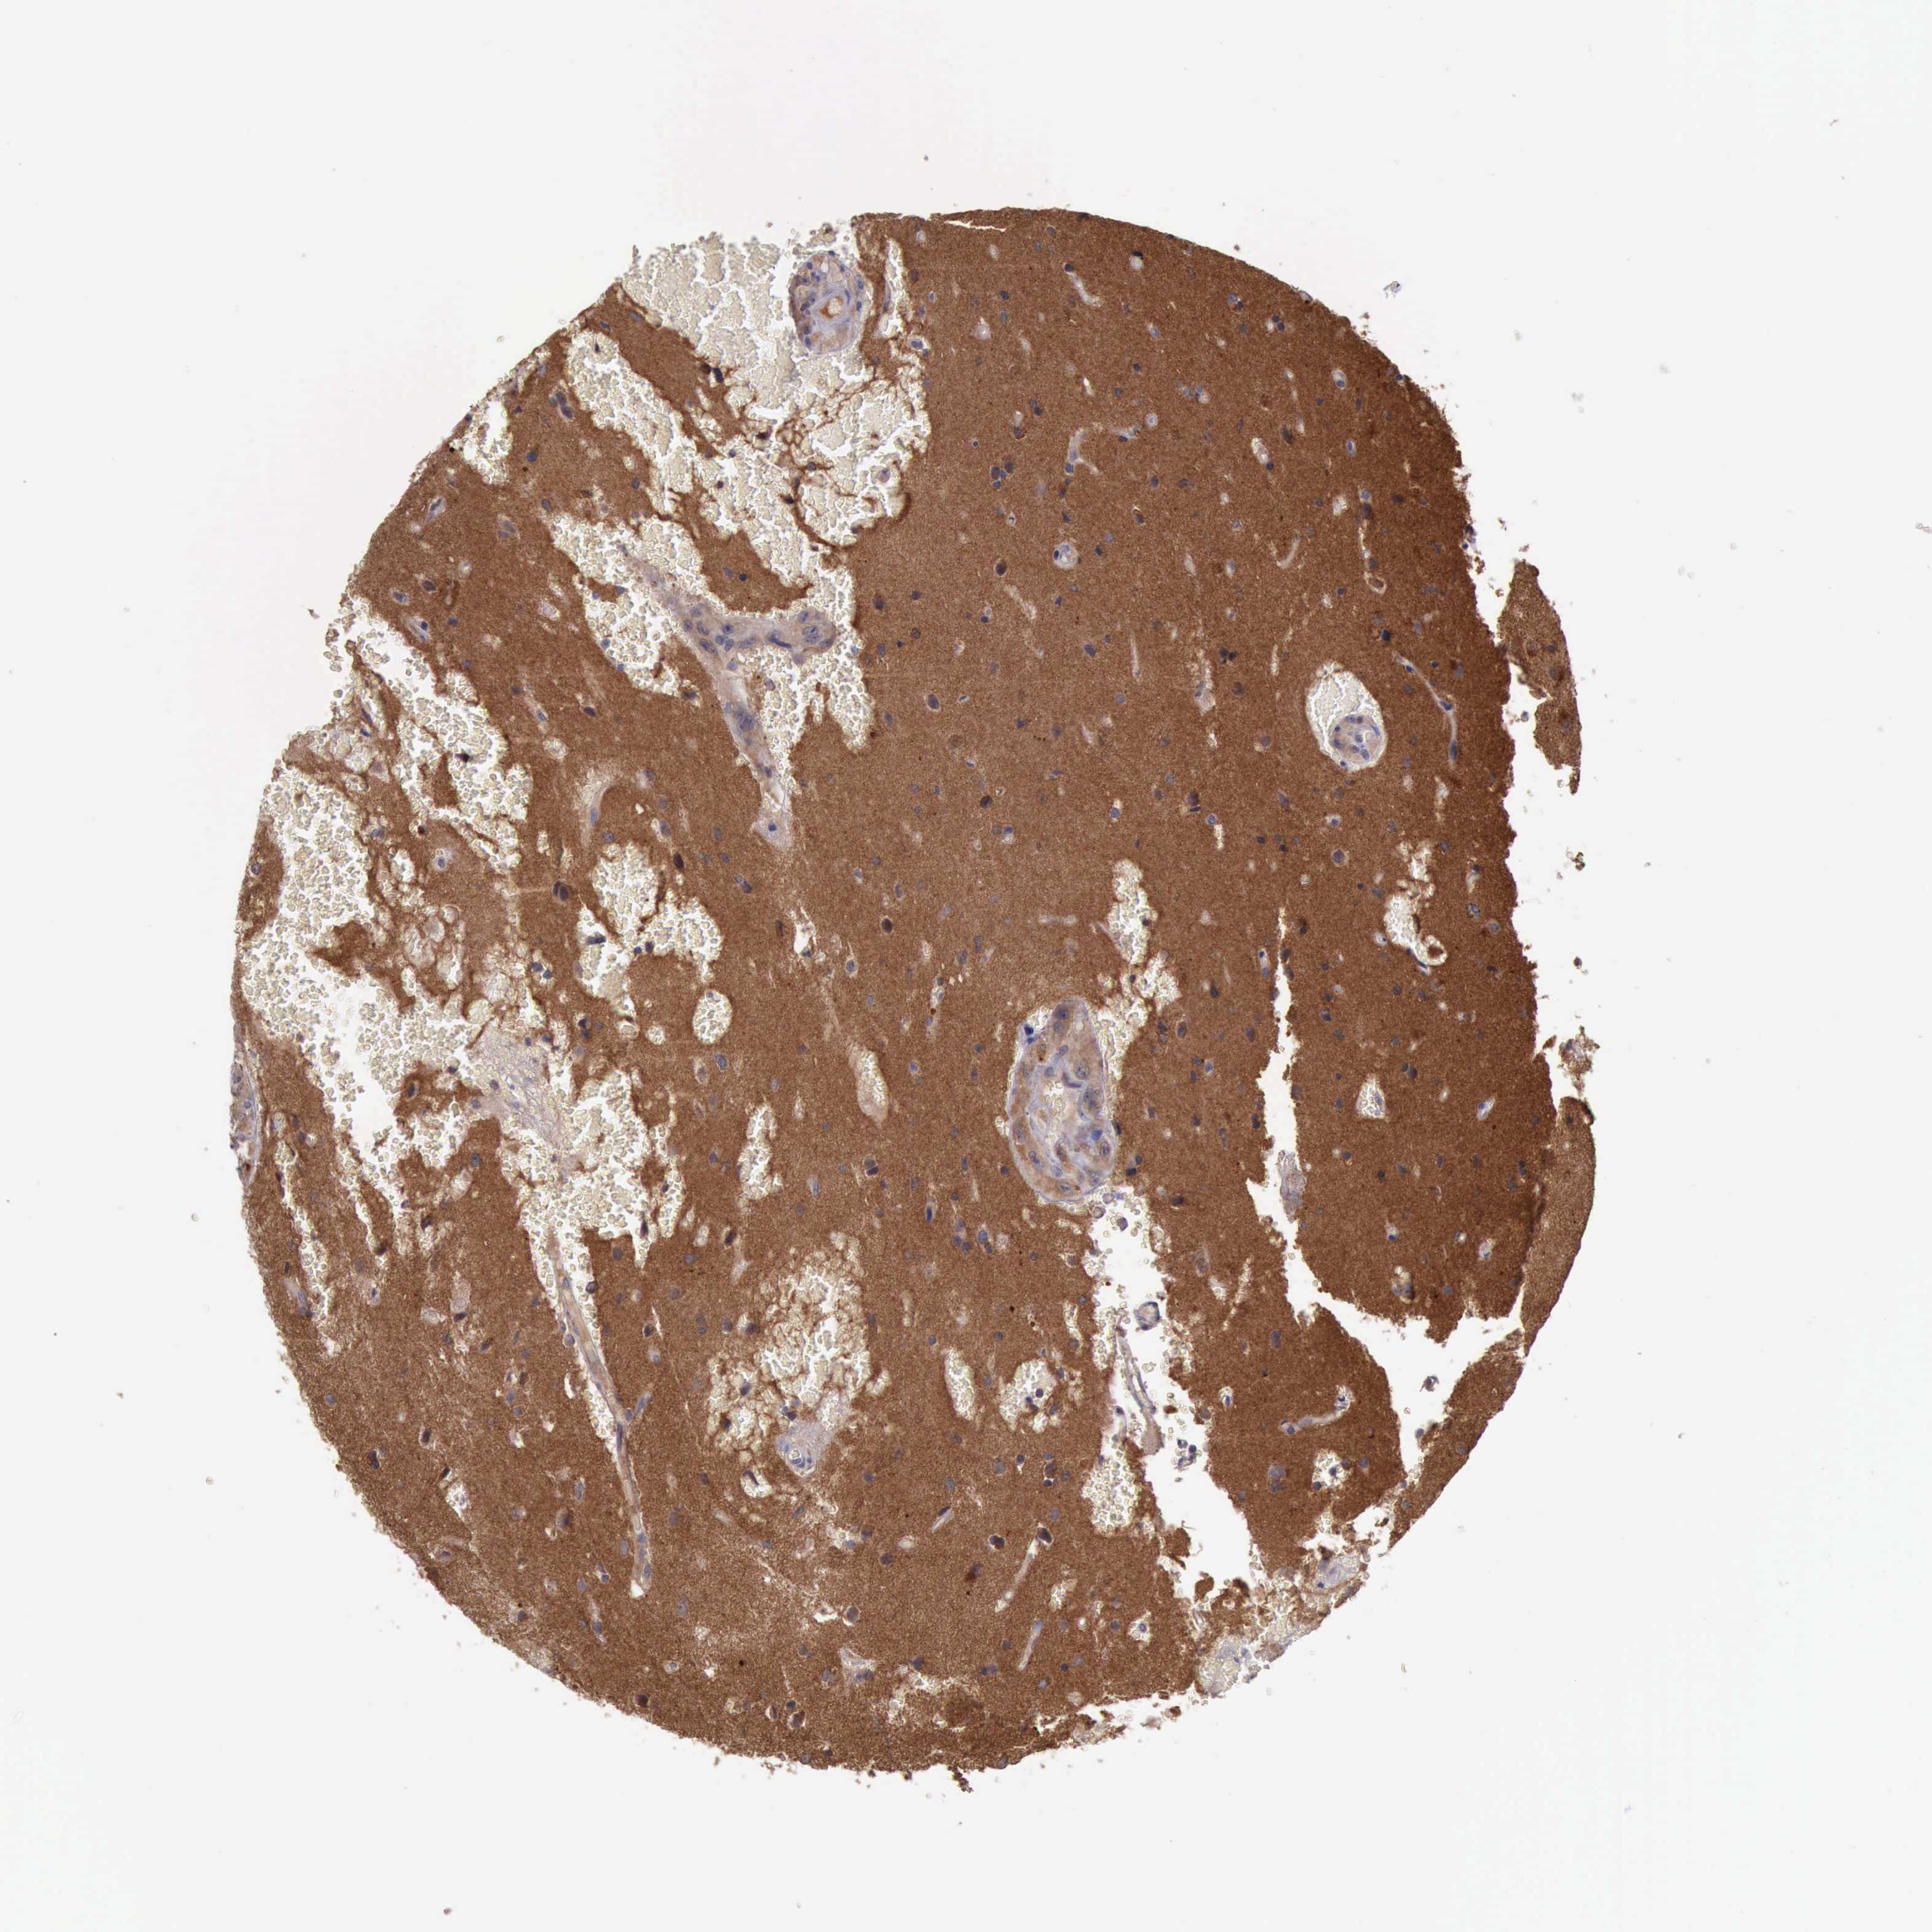

GLIOMA - Protein expressioni

A mouse-over function shows sample information and annotation data. Click on an image to view it in a full screen mode. Samples can be filtered based on level of antibody staining by selecting one or several of the following categories: high, medium, low and not detected. The assay and annotation is described here.

Note that samples used for immunohistochemistry by the Human Protein Atlas do not correspond to samples in the TCGA dataset.

Antibody stainingi

Antibody staining in the annotated cell types in the current human tissue is reported as not detected, low, medium, or high, based on conventional immunohistochemistry profiling in selected tissues. This score is based on the combination of the staining intensity and fraction of stained cells.

Each image is clickable and will lead to virtual microscopy that enables deeper exploration of all samples and also displays staining intensity scores, fraction scores and subcellular localization as well as patient and tissue information for each sample.

Antibody HPA001114

Antibody HPA042505

Staining

High

Medium

Low

Not detected

Intensity

Strong

Moderate

Weak

Negative

Quantity

>75%

75%-25%

<25%

None

Location

Nuclear

Cytoplasmic/membranous

Cytoplasmic/membranous,nuclear

Glioma, malignant, High grade

Glioma, malignant, Low grade